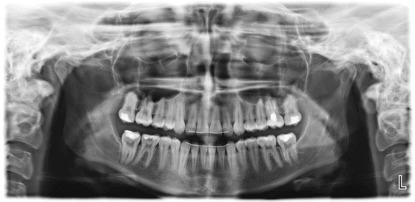

Панорамна снимка на зъби (OPG)

Панорамната зъбна снимка (OPG) обхваща цялото съзъбие, челюстните стави и пода на синусите. С нейна помощ се откриват непоникнали (ретинирани) зъби, включително мъдреци, пародонтални проблеми, кисти, тумори, фрактури и др. Следи се развитието на зародишите и корекцията на захапката при ортодонтско лечение. Използва се както за сваляне на статуса при първоначален преглед, така и за периодичен контрол на състоянието.